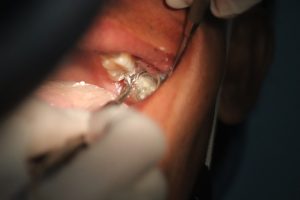

在面對臉上的坑洞時,現代醫學提供了多種療程選擇。常見的療程包括微針療法、激光治療和填充劑注射等。微針療法透過在皮膚上創造微小的傷口,促進膠原蛋白的生成,從而改善皮膚的質地和外觀。這種方法相對溫和,適合大多數人群。 激光治療則是利用高能量的光束來去除受損的皮膚層,促進新皮膚的生長。這種療程效果顯著,但通常需要較長的恢復時間。填充劑注射則是通過直接填充坑洞來改善外觀,效果立竿見影,但需要定期維護。根據個人的需求和皮膚狀況,選擇合適的療程至關重要。

儘管坑洞重建療程能夠帶來顯著效果,但仍然存在一定風險和副作用。常見的不適反應包括紅腫、疼痛或輕微出血等,這些通常是暫時性的,不會對健康造成長期影響。然而,在少數情況下,也可能出現過敏反應或感染等較為嚴重的情況,因此選擇經驗豐富且專業的醫師進行治療至關重要。 在接受任何治療之前,了解可能出現的風險是非常重要的。與醫師充分溝通自己的健康狀況及過敏史,可以幫助降低風險。此外,在術後如發現異常情況,如持續紅腫或疼痛加劇等,應及時就醫,以確保安全。